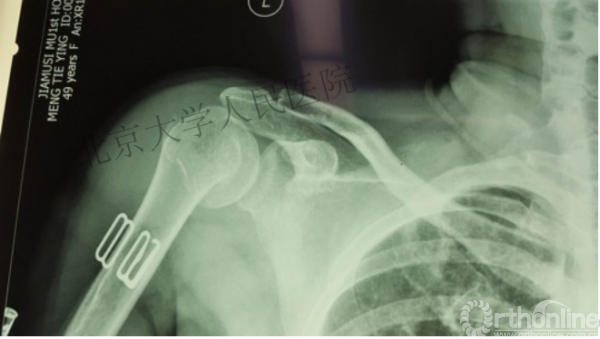

另一个留有遗憾的病例,您的选择?PHN?

临床中的广泛内固定治疗不断地提出思考